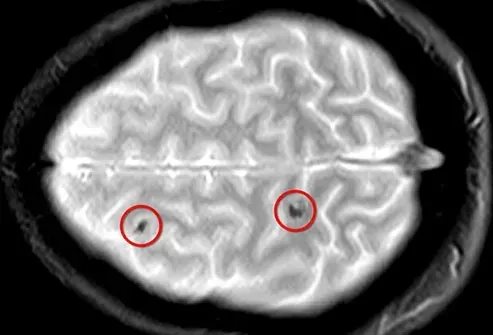

Sclérose en plaques

Lorsque vous avez une SP, votre système immunitaire attaque les nerfs de votre cerveau et de votre moelle épinière. Votre corps envoie des globules blancs pour nuire à la myéline la couche d'isolation autour des nerfs. Cela provoque des lésions nerveuses et perturbe le flux d'informations vers et depuis le cerveau. Au fil du temps, le tissu cicatriciel se forme sur les nerfs et crée des lésions. Ces changements conduisent à des choses comme les tremblements d'engourdissements et les problèmes de vision.